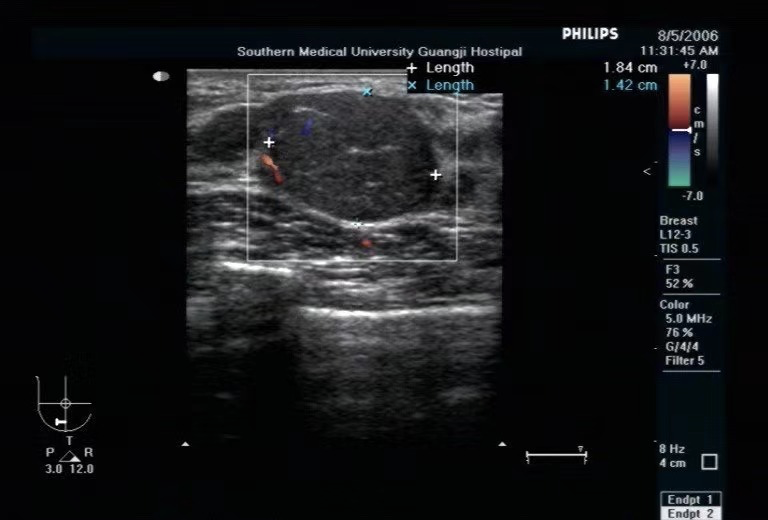

再來説説乳腺囊腫。

簡單來説,乳腺囊腫就是乳腺裏面長了一個「水泡兒」。

一般而言,乳腺囊腫是一個光滑的、容易移動的圓形或橢圓形腫塊,有可能自己摸得到,也有可能摸不到。